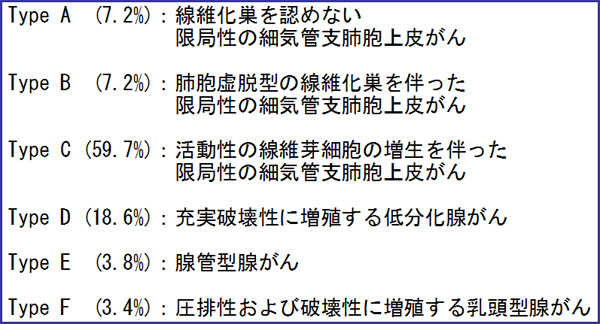

末梢型小型肺腺がんに対しては、予後を考慮した野口分類が日本では広く使われてきて、現在も一部で用いられています。野口Type A, Type Bは早期肺がん例であり、切除後は良好な予後が期待されます。

野口分類(末梢型小型肺腺がん)